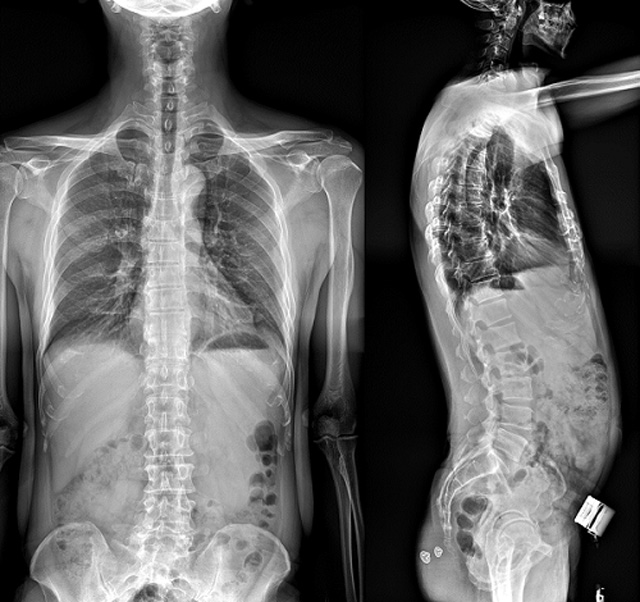

(7)全身拼接功能对有较大尺寸全脊柱拼接图接桂成金下股分成几次拍摄,再经过秋件开在骨科开展的全脊柱畸形矫治工作中,虽然CT. MRI也能获取全脊柱影像,接图像,以便于长度、角度、力线等测量和察脊柱在重力情况下但不能进行立位检查,无法观全景观察。全身拼接功能是高等级DR摄取患者立位全下的功能状态图像,因此采用动态医院特别看重的动态DR功能之一。注:图中Cobb脊柱正侧位图像是首选的检查方法角度的大小是反映侧弯严重程度的一个标准。